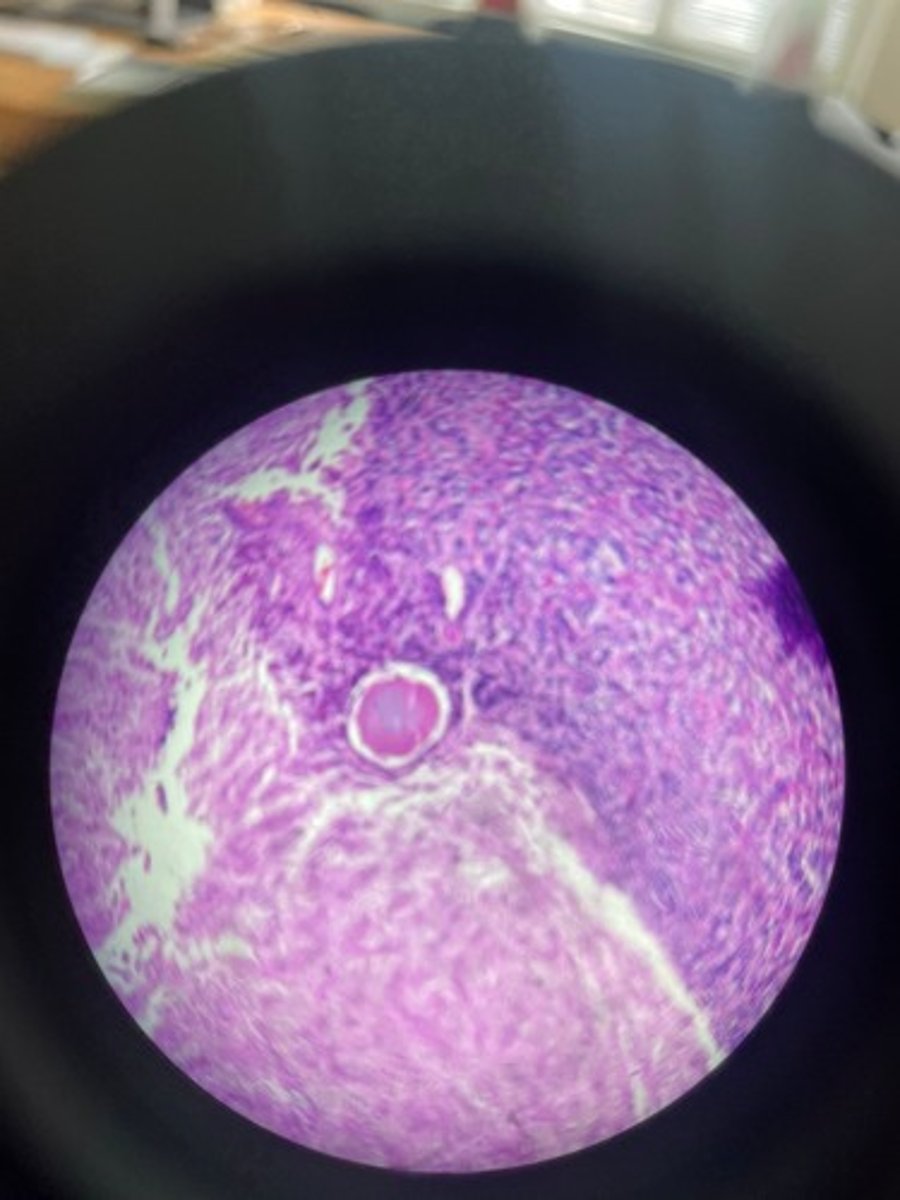

Lymph node HE

Lymph node HE

Lymph node HE

lymph node HE

Lymph node HE

Lymph nodes HE